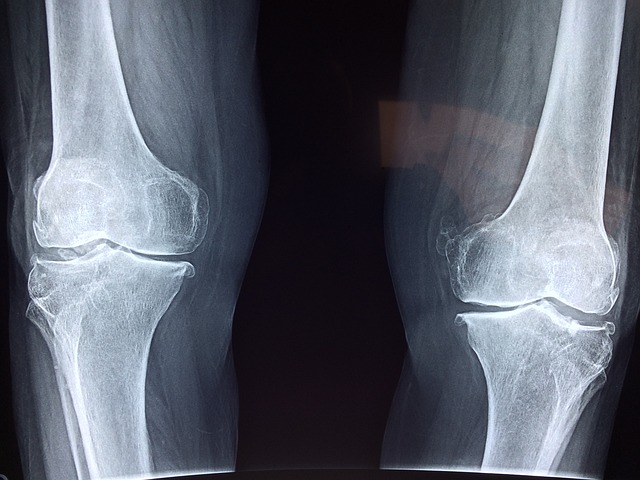

4.3 영상 검사

- X-ray

- 관절 공간의 축소, 연골 손상 확인.